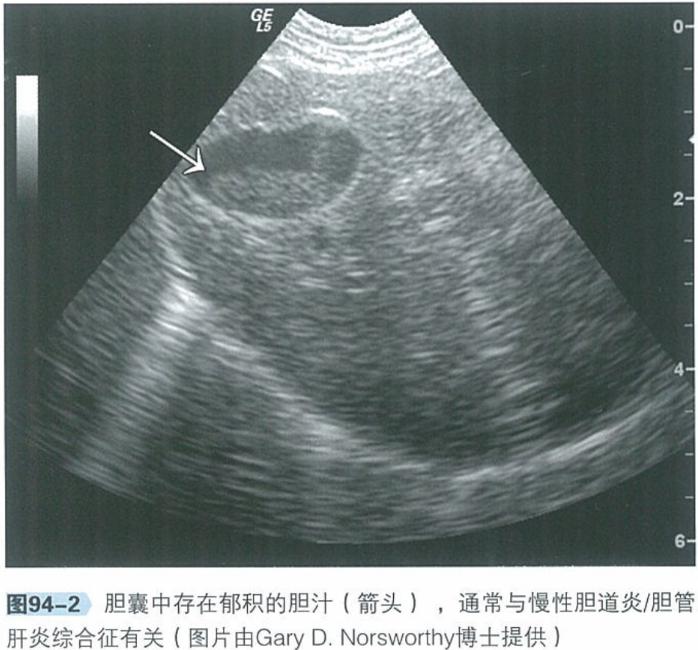

b.腹部超声:腹部超声是检查肝脏、胆管系统及胰腺实质结构极为有用的工具。肝脏回声通常正常,胆管及胆囊可见异常,包括胆总管、胆囊或肝内胆管扩张、部分或完全阻塞,胆汁淤积。

犬猫呕吐的鉴别诊断,犬猫呕吐的诊断和治疗